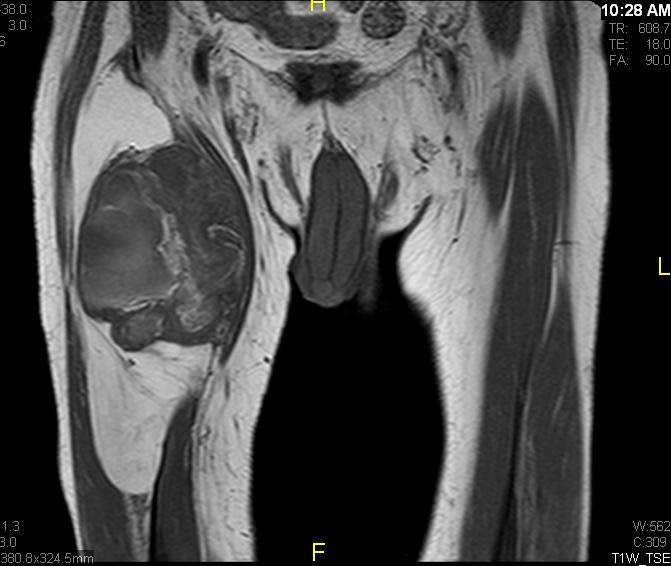

Fig. 1 & 2 Magnetic Resonance Image shows a large heterogeneous mass in the left gluteal region with low intensity signal on Axial (Fig. 1) and Coronal (Fig. 2) T1-weighted images admixed with some high signal areas indicative of fatty tissue. Higher intensity signal is visible compatible with hemorrhage or necrotic tissue. The mass involve the central portion of the left iliac bone.

Fig. 7 & 8 Magnetic Resonance Image shows a large heterogeneous mass in the right thigh with low intensity signal on Axial (Fig. 7) and Coronal (Fig. 8) T1-weighted images admixed with high signal areas. The high signal areas represent low grade fatty tissue and low signal the dedifferentiated areas. Higher intensity signal is visible compatible with hemorrhage or necrotic tissue.